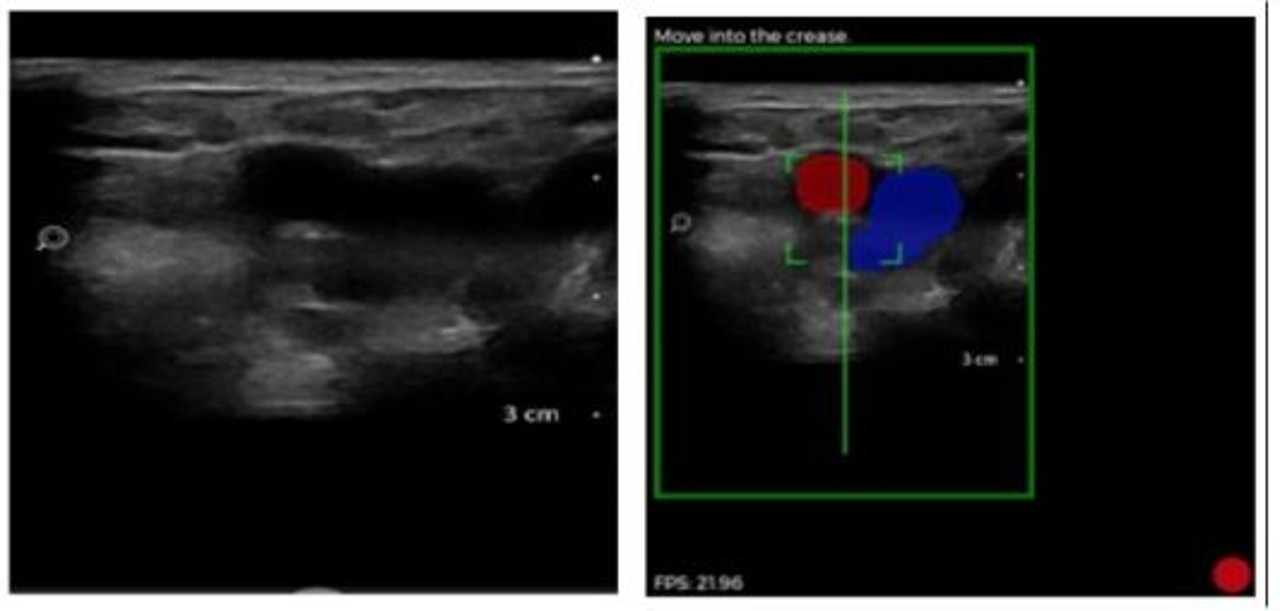

Potsdam - April 2024. Mit künstlicher Intelligenz (KI) tiefe Venenthrombosen (TVT) erkennen und somit Leben retten, das hat sich ThinkSono, ein eHealth- Start-up mit Sitz in Potsdam und London, zur Hauptaufgabe gemacht. Die Guidance Software von ThinkSono ist die weltweit erste Software, die es nicht im Ultraschall geschultem medizinischen Personal ermöglicht, Patienten mit Verdacht auf Blutgerinnsel (TVT) zu scannen und die Daten zur Überprüfung durch qualifizierte Kliniker zu senden, wodurch der klinische Ablauf verbessert wird.

Das 2016 gegründete Unternehmen ThinkSono hat die weltweit erste KI-Echtzeit-Ultraschallsoft-ware entwickelt, mit der medizinisches Personal ohne Ultraschallkenntnisse TVT-Scans durchführen kann. Diese Technologie adressiert den weltweit ungedeckten medizinischen Bedarf an einer besseren TVT-Erkennung. Darüber hinaus entwickelt ThinkSono Schulungslösungen für andere KI-Ultraschallanwendungen, um den Zugang zur Ultraschallbildgebung zu verbessern und nicht für Ultraschall geschultes Gesundheitspersonal für die Durchführung wichtiger Ultraschall-untersuchungen zu qualifizieren. Die TVT-Lösung von ThinkSono wurde bereits in Krankenhäusern in Großbritannien und der EU erprobt und wird nun auch in den USA eingeführt.